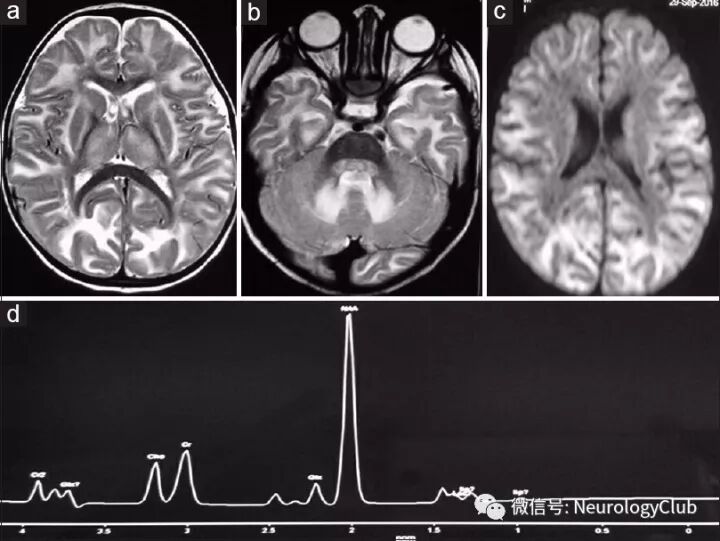

头颅MRI可见双侧齿状核和脑白质对称T2WI高信号,累及皮质下弓形纤维,DWI上呈弥散受限。未见脑积水,占位效应或中线移位。左侧顶部白质单体素MRS可见N-乙酰天冬氨酸(NAA)峰明显升高,肌酸和胆碱峰正常。

(图:a-b:T2WI可见双侧脑白质及齿状核高信号病灶伴弓形纤维受累;c:DWI上皮质下白质病灶呈弥散受限;d:右顶部白质单体素MRS可见NAA峰明显升高,而肌酸和胆碱峰正常)

Canavan病,也称为脑白质海绵样变性或海绵状脑白质营养不良,是一种常染色体隐性遗传病,因位于17号染色体短臂的天冬氨酸酰基转移酶(ASPA)基因突变所致,引起N-乙酰天冬氨酸酰化酶缺乏,导致NAA在患者尿液、血浆及脑内过度聚积。影像学可见双侧弥漫对称白质T2WI高信号,累及皮质下弓形纤维。病灶一般无强化。基底节和小脑白质亦可受累。影像学鉴别诊断包括异染性脑白质营养不良、肾上腺脑白质营养不良、佩-梅病(Pelizaeus-Merzbacher disease,PMD)和亚历山大病。异染性脑白质营养不良和肾上腺脑白质营养不良可见双侧对称性T2WI白质高信号,但皮质下白质不受累。此外,肾上腺脑白质营养不良常先累及双侧额叶白质,由前向后进展,可见病灶边缘强化。PMD也可累及皮质下弓形纤维,但通常伴有明显的小脑萎缩和进行性脑沟增宽。此外,PMD患者无巨头畸形,MRS上NAA水平正常。现认为,细胞毒性水肿伴相应的DWI弥散受限是婴儿Canavan病的早期标志。类似的改变在本例中亦可见到。